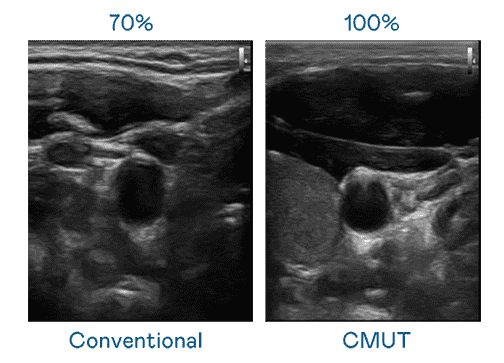

CMUT 技术是一种用电容式微机电元件来产生超音波讯号的技术。。。。与传统 PZT 压电式技术相比,,,,CMUT 频宽增加 30%,,,,更宽频的超音波讯号让影像解析度大幅提升,,,是实现高影像品质医疗超音波扫描、、、、促进精准医疗发展的关键技术。。。

大频宽带来超清晰影像

超音波影像的解析度高低,,,,首先取决于探头能发出的讯号频宽。。。尊时凯龙 CMUT 可提供高清晰的超音波讯号,,提供高频宽、、、、高灵敏度、、、影像纹理细节更高的超音波影像,,协助医护人员缩短影像判读时间及利用精准的医疗影像进行诊断。。。。